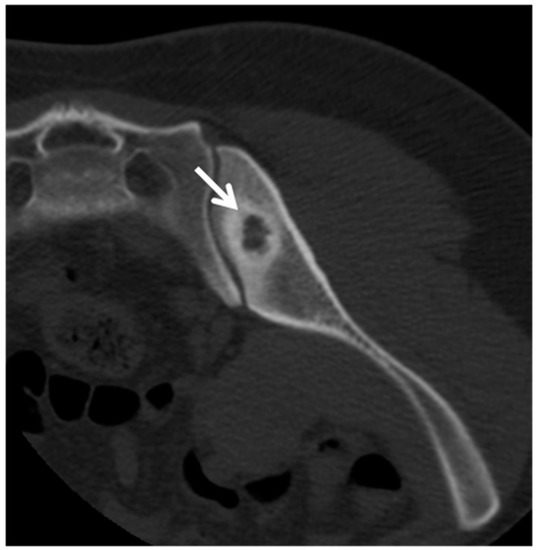

9. Spondylodiscitis

- Michel, S.C.; Pfirrmann, C.W.; Boos, N.; Hodler, J. CT-guided core biopsy of subchondral bone and intervertebral space in suspected spondylodiskitis. AJR Am. J. Roentgenol. 2006, 186, 977–980. [Google Scholar] [CrossRef] [PubMed]

- Rimondi, E.; Rossi, G.; Bartalena, T.; Ciminari, R.; Alberghini, M.; Ruggieri, P.; Errani, C.; Angelini, A.; Calabrò, T.; Abati, C.N.; et al. Percutaneous CT-guided biopsy of the musculoskeletal system: Results of 2027 cases. Eur. J. Radiol. 2011, 77, 34–42. [Google Scholar] [CrossRef]

- Jevtic, V. Vertebral infection. Eur. Radiol. 2004, 14 (Suppl. 3), E43–E52. [Google Scholar] [CrossRef]

- Sharif, H.S.; Morgan, J.L.; Al Shahed, M.S.; Al Thagafi, M.Y. Role of CT and MR imaging in the management of tuberculous spondylitis. Radiol. Clin. N. Am. 1995, 33, 787–804. [Google Scholar]